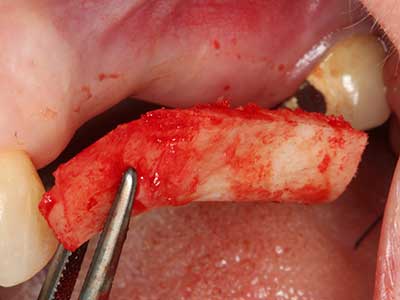

En la extracción de bloques óseos la piezocirugía también presenta ventajas adicionales: Además de la alta precisión en la osteotomía que ya se ha descrito antes, se ha comprobado que el uso de los delgados insertos de sierra resulta especialmente cuidadosas con el hueso. Frente a esto, sobre todo cuando se usan las fresas de Lindemann, cabe esperar pérdidas en la extracción significativamente más altas debido al mayor grosor de la parte frontal del cabezal (Lakshmiganthan, Gokulanathan et al. 2012). La separación basal que se necesita en particular en los injertos de bloque extraídos de forma retromolar se ve facilitada mediante sierras perpendiculares especialmente previstas a tal fin, lo que permite considerar que la cirugía piezoeléctrica es un procedimiento preciso y seguro para la obtención de bloques de hueso en el área retromolar (Happe 2007) (fig. 1-12).

Fig. 1: Preparación de una tapa ósea conforme con Piezomed (W&H, Salzburgo, Austria)

Fig. 3: La separación basal del bloque se ve facilitada con piezas dotadas de una angulación especial.

Fig. 4: Con la rasqueta ósea se obtienen virutas adicionales de hueso autógeno.